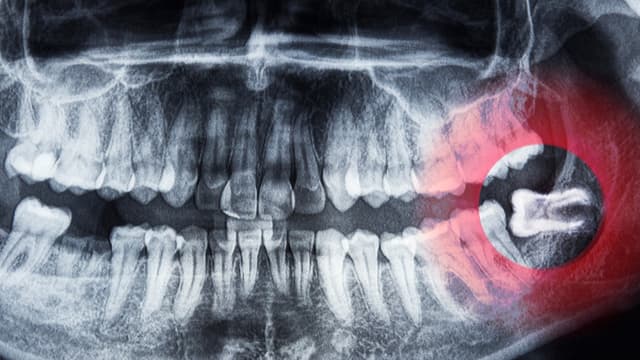

Giải đáp: Khi nào nhổ răng khôn để tránh biến chứng nguy hiểm

Khi nào nhổ răng khôn là câu hỏi được nhiều người quan tâm, bởi răng khôn có thể âm thầm gây ra nhiều vấn đề sức khỏe răng miệng nếu không được theo dõi và xử lý kịp thời. Vậy đâu là thời điểm lý tưởng để can thiệp? Bài viết dưới đây sẽ giúp […]